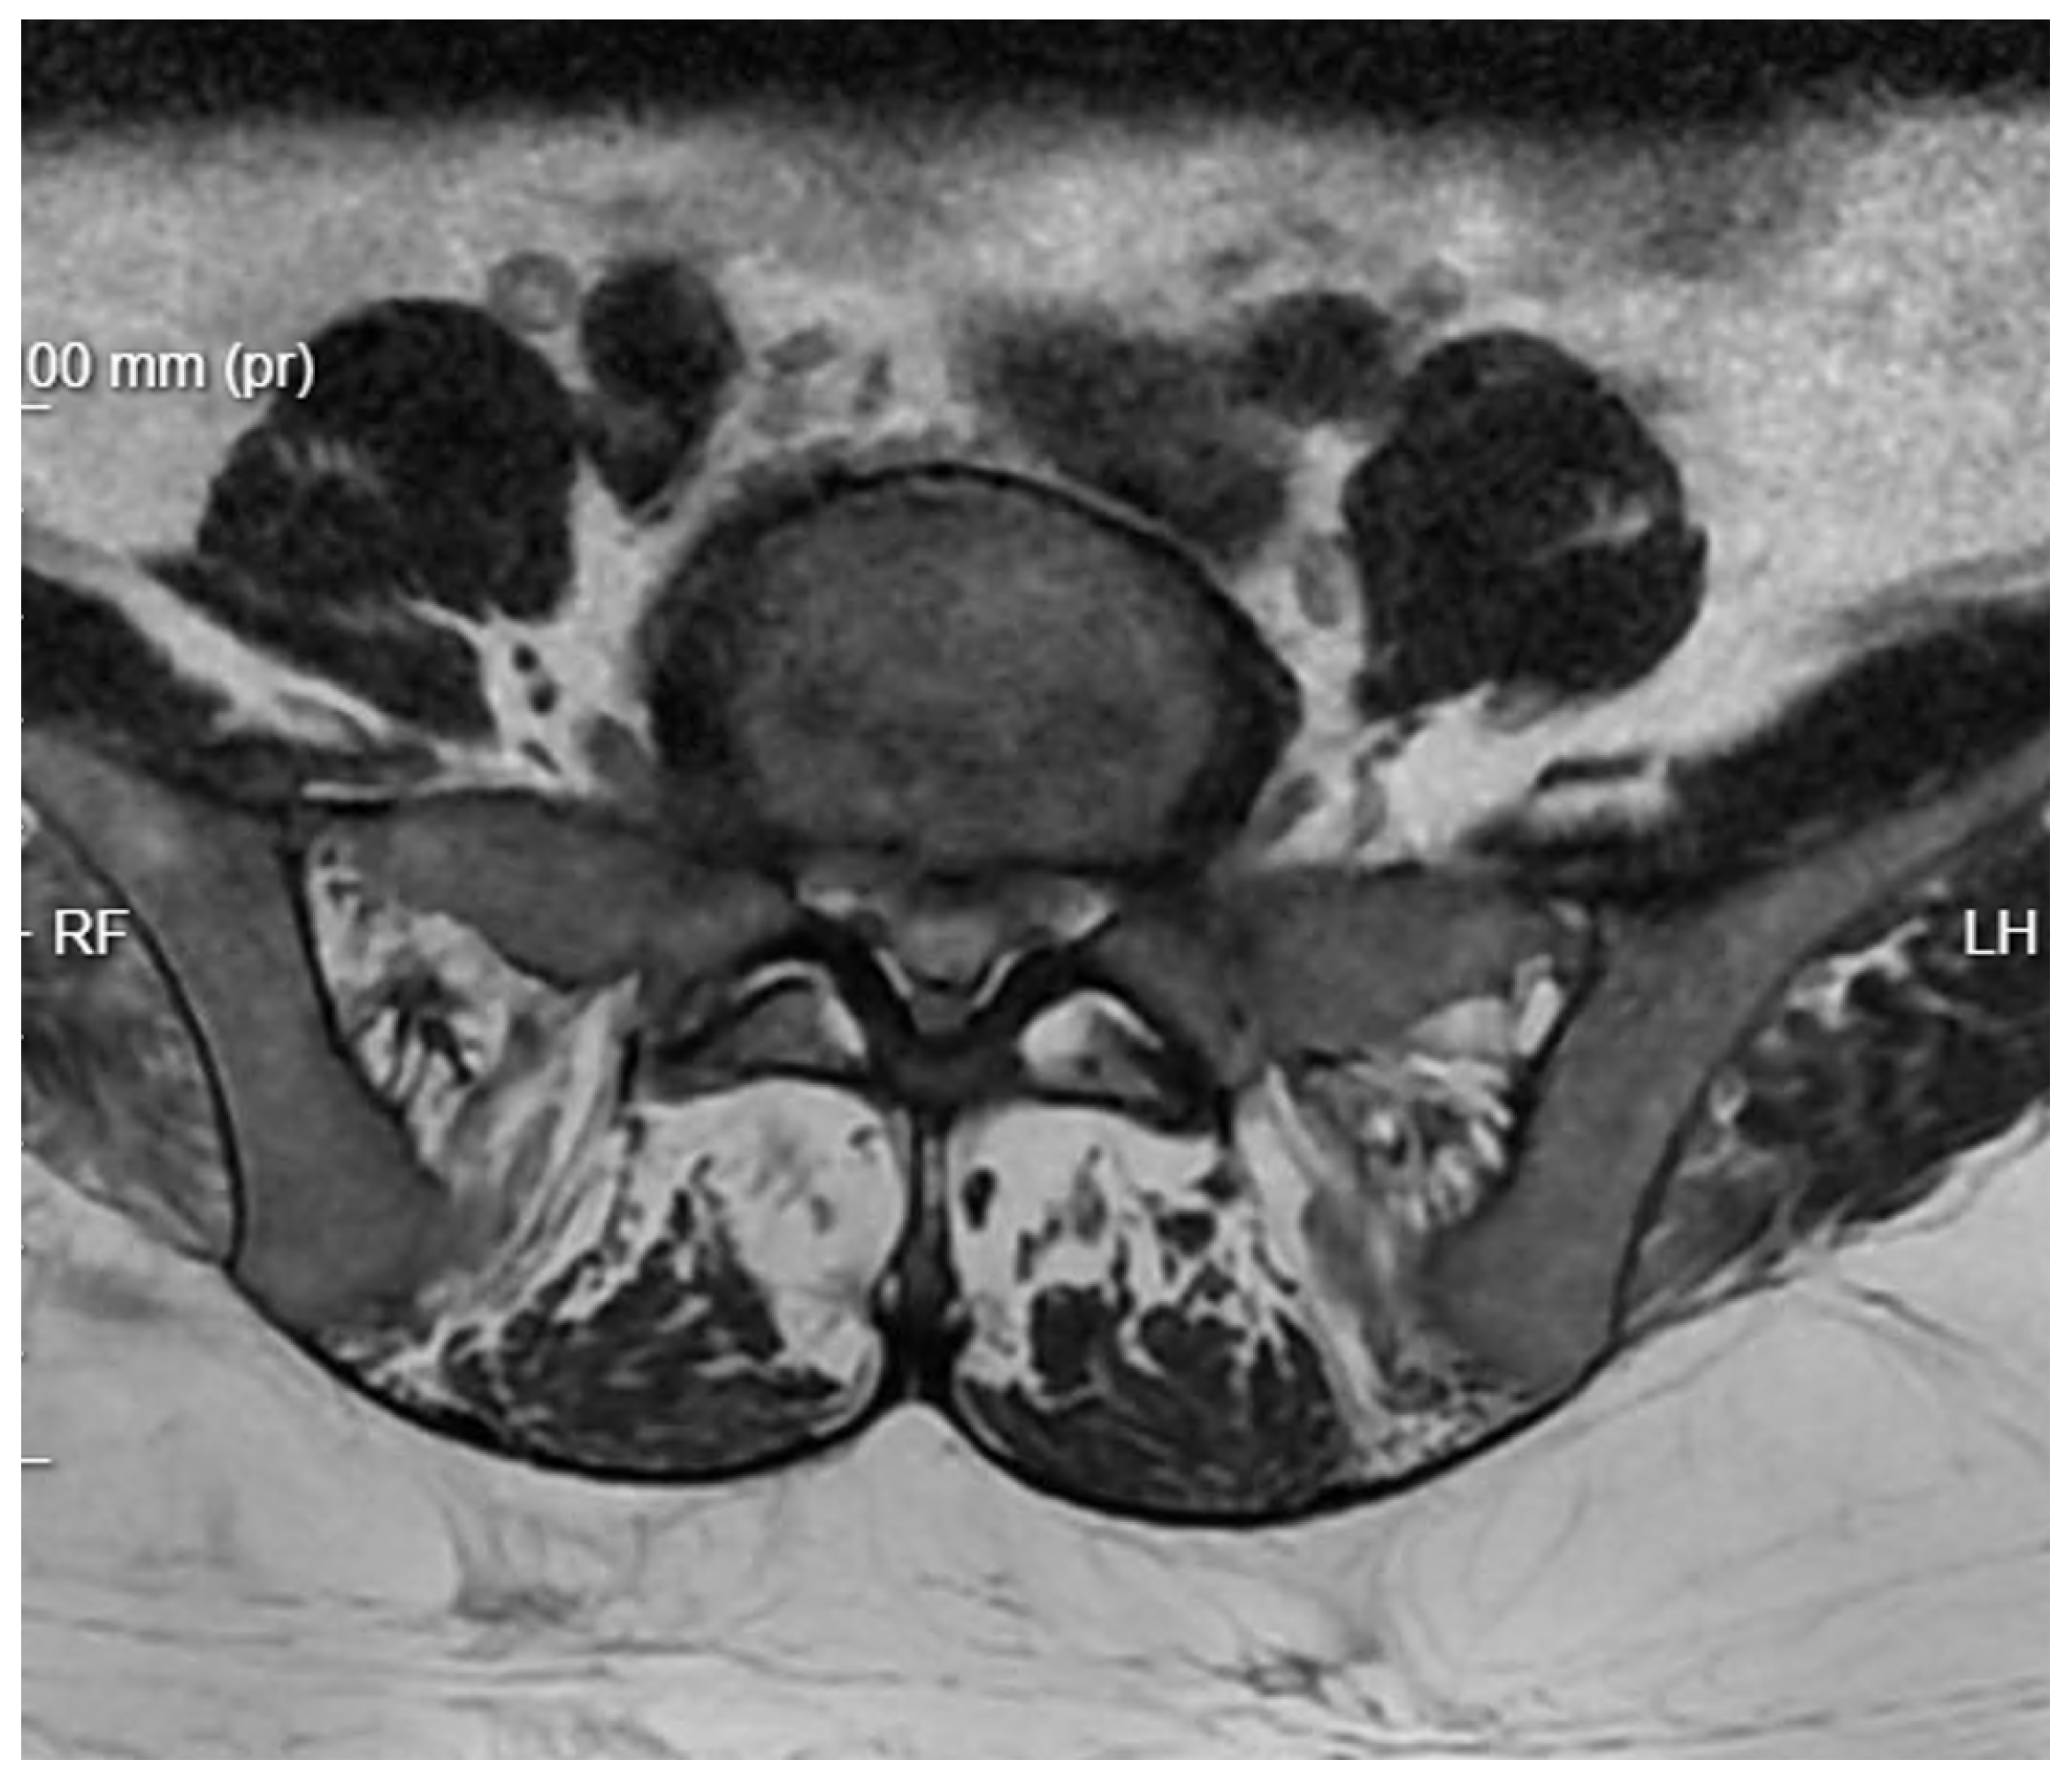

Patient Background: A 50-year-old female patient with a body mass index (BMI) of 32 was admitted to the neurology emergency department due to an acute spinal pain syndrome persisting for three days. The pain, VAS 7, was located in the lower spine, radiating bilaterally to both lower limbs, and exacerbated by movement. The patient had undergone a gynecological procedure under epidural anesthesia one month prior to this episode. Initial MRI (Figure 2) of the spine revealed a collapse of the L5/S1 space with a small central protrusion. The disc signal raised suspicion of early inflammatory changes in the eyes of the consulting neurosurgeon, though the radiologist conclusively denied inflammatory features. The patient presented with slightly elevated inflammatory markers, with a CRP level of 20 mg/L.

Figure 2. Pre-operative T2 axial MRI image at the L5/S1 level on the day of the patient’s admission to the neurology department.